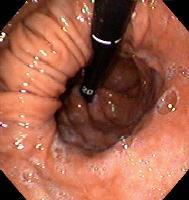

Dx?

Hiatal hernia

(Gastric folds present above the diaphragm, which is the circular constricted area)

What is causing this endoscopic finding?

What symptom may the patient present with?

GERD leading to a bleeding ulcer

Hematemesis